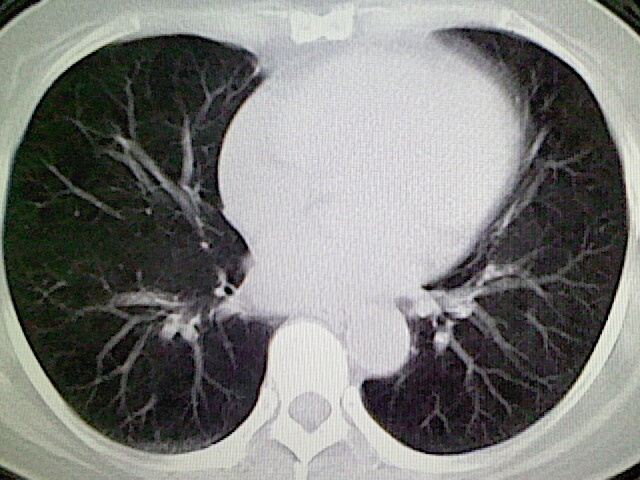

女,52岁,咳嗽,咳痰多日

左下肺陈旧纤维索条!

左肺舌段炎性改变

我见过几例,为炎症后纤维条索

慢性炎症后改变

考虑慢性炎性病灶粘连牵拉改变。

左肺舌叶纤维锁条病变。

左肺上叶下舌段炎症并局部胸膜反应。

左肺舌叶纤维索条影。

左肺舌叶段陈旧性病变

左肺舌段炎性反应。片子的质量太不好了。

左肺舌段炎性

炎性改变

左肺舌叶纤维索条影